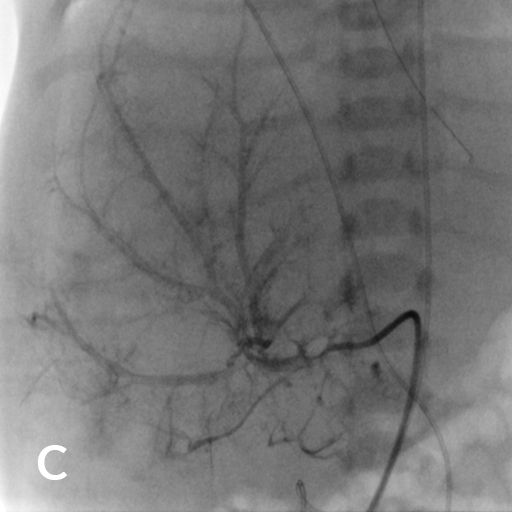

7 jähriger Junge mit Kurzdarmsyndrom und Leberzirrhose

Als Folgen des Pfortaderhochdrucks war die Milz vergrößert (Splenomegalie) und es traten Krampfadern der Speiseröhre (Ösophagusvarizen) auf. Um den Hochdruck zu entlasten wurde ein TIPS angelegt. Dazu wird aus der rechten Lebervene (A) mit einer speziellen Nadel ein Pfortaderast punktiert (B). Anschließend wird die Pfortader mit einem Draht sondiert (C) und die geschaffene Verbindung mit einem Ballon aufgedehnt und anschließend mittels Gefäßstütze (Stent) geschient (D). Durch diese künstliche Verbindung kann das Pfortadersytem deutlich druckentlastet werden.

Wissenschaftliche Abbildung TIPS